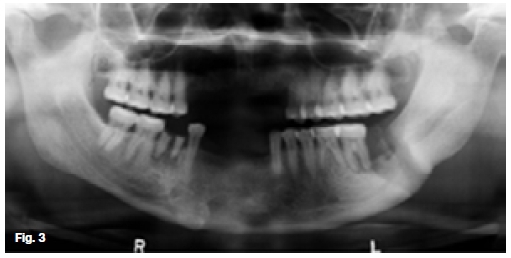

The upper two figures show a case in which there are facial scars of a recurring infection while the pantomo-graph shows ill-defined multilocular radiolucencies with enlargement of the trabecular spaces, suggestive of the presence of a chronic osteomyelitis affecting the hemi-andible on the left side. There are also features demonstrating the formation of sequestra. The case shown in the lower figures started after an assault which had caused a fracture at the angle of the left mandible. A tooth in line of the fracture was removed and since then a draining sinus had developed which showed signs of healing after the removal of sequestrum. In both cases a diagnosis of chronic actionomycotic osteomyelitis of the mandible was made, a rare condition found in 10% of all cervicofacial actinomycosis cases. When it occurs, the radiographic changes are not characteristic. Actionomycosis is a specific infectious disease, primarily caused by the organism Actinomycis Israeli. It affects men twice as frequently as women and is most often encountered in the 20-50 year age groups. The cervicofacial type of actinomycosis is by far the most common, with pulmonary and abdominal actino-mycosis occurring less frequently. However, because of its variable clinical manifestations and difficulty in isolating the causative agent, the diagnosis is often delayed. The actinomycotic infection is not a pure infection; it probably is a result of a synergism between microbes of the ray fungus group and other anaerobic microbes. Clinically, the infection has a prolonged course. The first sign is the appearance of a red to dark blue, nodular infiltration, often located within the skin of the subman-dibular area or angle of the jaw. Untreated, the infection spreads along anatomical planes, producing a hard infiltrate with simultaneous occurrence of draining abscesses. The exudate may contain small yellow granules, termed "sulphur granules", which consist of colonies of actinomyces which tends to be diagnostic. Enlargement of regional lymphnodes is seldom observed and the general status of the patients is unimpaired.